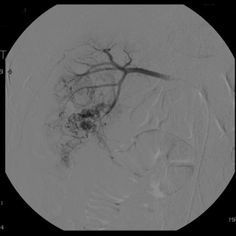

Renal Cell Carcinoma Normal Idiopathic, related to cigarette Can be caused by long term dialysis Develops from the renal tubules, destroying the kidney while it invades the blood vessels (IVC and renal vein), allowing spreading of malignant cells Symptoms: hematuria Common in males over 40 years old Radiographic Appearance: Angiography and ultrasound modality of choice, angiography: abnormal vascular ultrasound: composition of tumor along with invasion of renal vessels